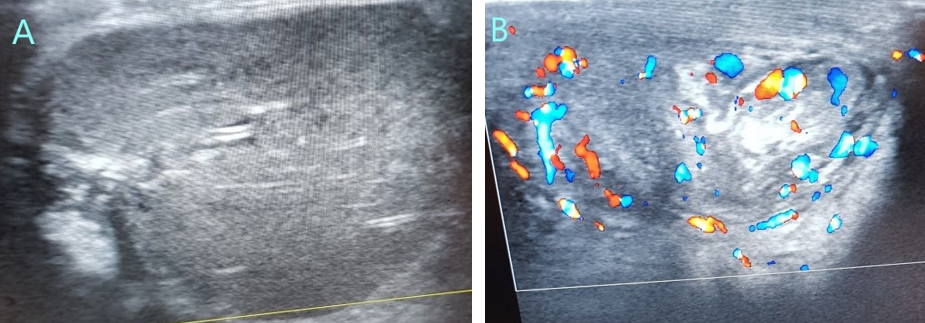

Hình

ảnh siêu âm Doppler tinh hoàn của bệnh nhi khi vào viện:

A. Nhu mô tinh hoàn giảm âm

không đều và không thấy tín hiệu mạch trong tinh hoàn

B. Hình ảnh xoáy nước